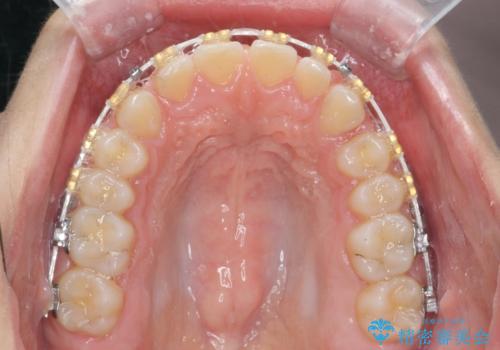

深い噛み合わせ、すきっ歯の改善 ワイヤーを用いたマルチブラケット矯正

- 矯正装置

- ワイヤー矯正

ワイヤーを用いたマルチブラケット矯正を行うことで深い噛み合わせを改善し、前歯の隙間もなくし審美的な歯列へと治療をおこなっていきます。

深い噛み合わせの改善は前歯の圧下が必要なため、治療期間が長期化することが多いです。